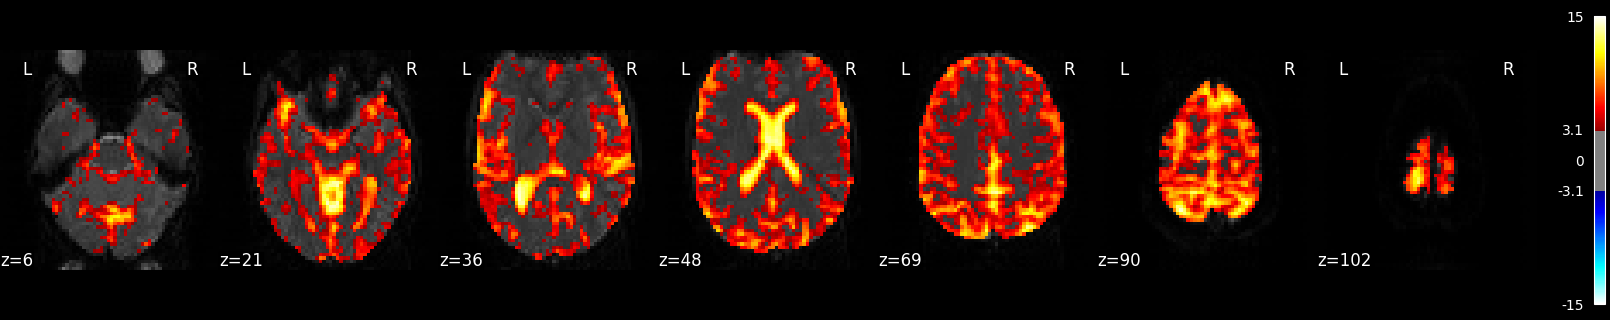

Plot R-squared¶

Because we stored the residuals, we can plot the R-squared: the proportion of explained variance of the GLM as a whole. Note that the R-squared is markedly lower deep down the brain, where there is more physiological noise and we are further away from the receive coils. However, R-Squared should be interpreted with a grain of salt. The R-squared value will necessarily increase with the addition of more factors (such as rest, active, drift, motion) into the GLM. Additionally, we are looking at the overall fit of the model, so we are unable to say whether a voxel/region has a large R-squared value because the voxel/region is responsive to the experiment (such as active or rest) or because the voxel/region fits the noise factors (such as drift or motion) that could be present in the GLM. To isolate the influence of the experiment, we can use an F-test as shown in the next section.

plotting.plot_stat_map(

fmri_glm.r_square[0],

bg_img=mean_img,

threshold=0.1,

display_mode="z",

cut_coords=7,

)

Calculate and Plot F-test¶

The F-test tells you how well the GLM fits effects of interest such as the active and rest conditions together. This is different from R-squared, which tells you how well the overall GLM fits the data, including active, rest and all the other columns in the design matrix such as drift and motion.

z_map_ftest, bg_img=mean_img, threshold=3.1, display_mode="z", cut_coords=7